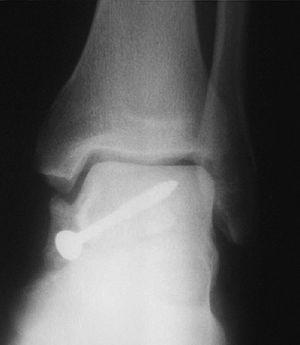

En las fracturas del cuerpo del astrágalo (7 casos) se realizó reducción abierta mediante un abordaje medial con osteotomía del maléolo tibial para visualizar todos los planos de la fractura y fijación interna (RAFI) con tornillos o agujas de Kirschner, o ambos. En 2 casos se realizó un abordaje bilateral debido a la complejidad de la fractura (fig. 6).

Fig. 6. --Fractura abierta de cuello de astrágalo (tipo III de Hawkins) y tratamiento realizado. Radiografías a los 16 meses.

Fig. 6. --Open fracture of the astragalus neck (Hawkins type III) and treatment carried out. Radiographies at 16 months.